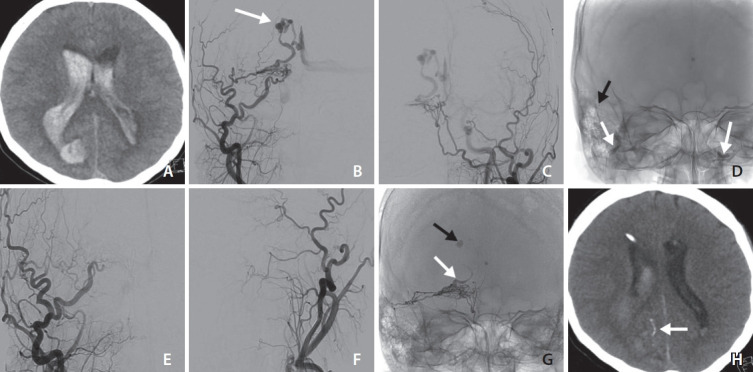

虽然这些事件在开放性神经外科手术中更常见,特别是那些涉及颅底的手术中,但在颅内硬膜动静脉瘘(davf)的Onyx栓塞术中发生心动过缓或心脏骤停的病例很少。我们提出一个病例治疗破裂的辅助枕骨DAVF。在将Squid注入脑膜中动脉期间,同时在双侧枕大动脉中充气球囊以控制DAVF栓塞期间的血流,患者出现窦性心动过缓的突然发作,在第二次注射Squid后复发。在暂时停止注射并放气后,第三次注射成功,没有并发症,完全排除了瘘管。

There are few documented cases of bradycardia or asystole occurring during Onyx embolization of intracranial dural arteriovenous fistulas (DAVFs), although these events are more commonly observed in open neurosurgical procedures, particularly those involving the skull base. We present a case treated for a ruptured paramedian occipital DAVF. During the administration of Squid into the middle meningeal artery, while balloons were inflated in the large occipital arteries bilaterally to control the flow during embolization of the DAVF, the patient experienced an abrupt episode of sinus bradycardia, which recurred after a second injection of Squid. After temporarily halting the injections and deflating the balloons, a third injection was successfully administered without complications, allowing total exclusion of the fistula.